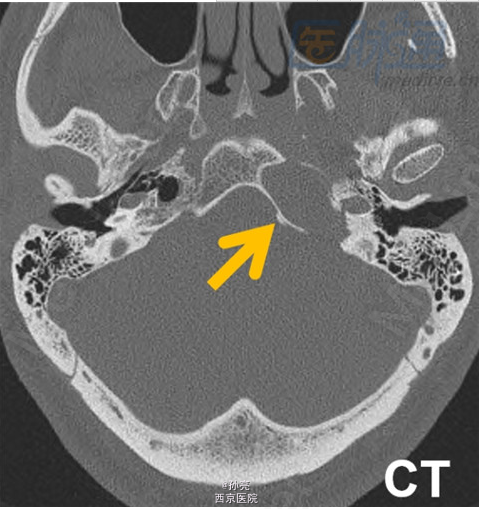

50岁男性,长期左侧耳聋。

CT检查多表现为颞骨岩尖部出现边界清楚的囊性膨胀性病变(图A箭头)。由于包块内血液分解产物和蛋白质碎片的积累,其在MRI检查时,多表现为T1和T2加权图像上的高信号影(图B箭头)。在MRI的T2加权图像上,可见到包块的周围有明显的低信号影包绕。而这主要是由含铁血黄素在局部的沉积所致(图C箭头)。此外,包块多无扩散受限(图D箭头)。